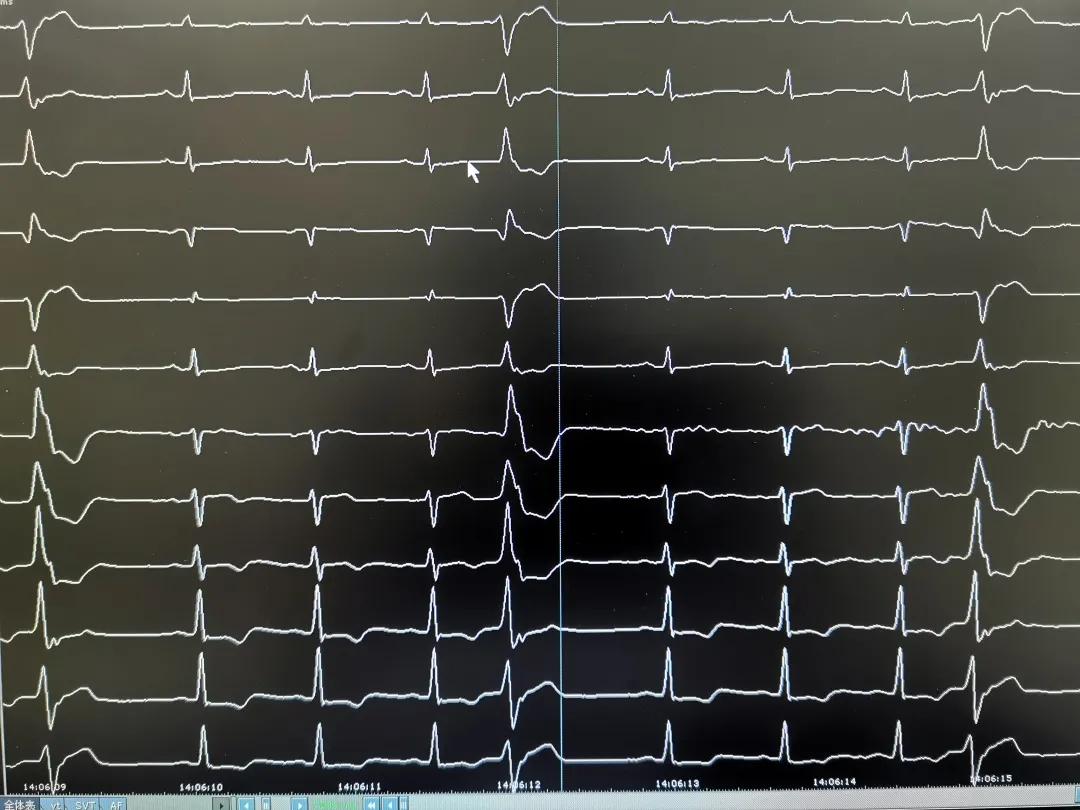

术后心电图

为进一步验证病灶是否真的已被阻断,有没有恢复的可能。术中,耿教授继续分次消融 2 分多钟,持续观察半小时,并静脉滴注异丙肾上腺素激发,仍然再无早搏,射频消融成功,手术台上的华先生瞬间即感受到了久违的胸腔内的舒适感。

由于术中仅仅给予华先生少量的局麻药物,术中无明显不适,术后 24 小时即可下床正常活动,术后三天复查 24 小时动态心电图,无室性早搏。目前,华先生已出院,脉搏保持在 60~70 次,未再服用抗心律失常药物,恢复良好,胃口也大大好转。